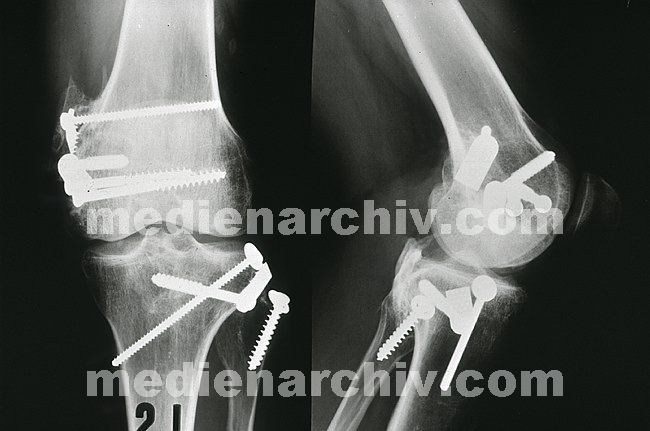

Roentgen-114

Röntgenaufnahme. Genagelte und geschraubte Knochen.